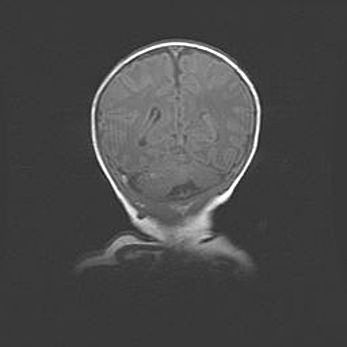

Открытая гидроцефалия.

Возраст: 6 месяцев 15 дней

Вес: 6200 г

Пол: женский

Окружность головы: 41 см

Срок гестации: 38 недель

Гидроцефалия головного мозга у новорожденных – это скопление избыточного количества цереброспинальной жидкости в головном мозге. Ее избыточное скопление в мозге приводит к патологическому расширению желудочков мозга (четырех полостей, расположенных в глубине белого вещества мозга, заполненных цереброспинальной жидкостью и связанных узкими проходами).

Открытый тип гидроцефалии (сообщающаяся) наблюдается тогда, когда нарушен механизм всасывания ликвора в системный кровоток. При этом типе причиной заболевания чаще всего является перенесенные ранее инфекции (например: менингит),  либо же наличие крови в субарахноидальном пространстве.